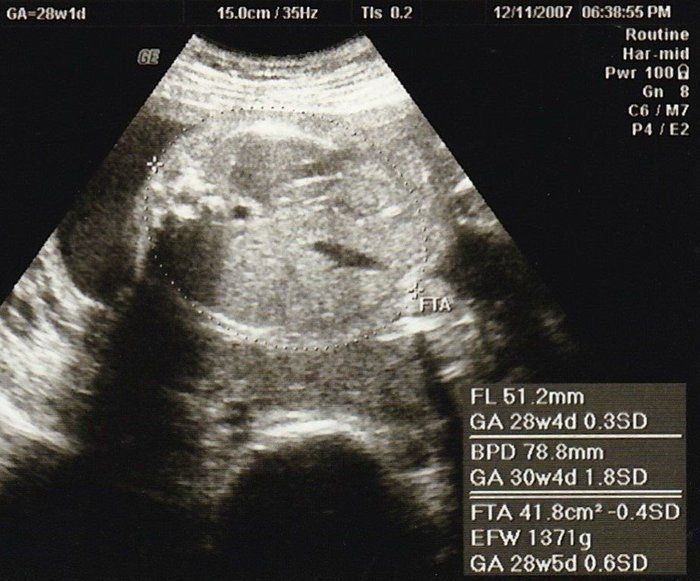

小吉さんの妊娠28週目のエコー写真

赤ちゃんの頭の大きさ(BPD)とお腹周り(AC)を測りました。赤ちゃんの成長は順調そのものでしたが、血液検査の結果で貧血の治療が必要となり、服薬はもちろんのこと、点滴のため週2回程度の病院通いが始まりました。

こちらは赤ちゃんのお尻の写真です。中央右寄り、お尻が上を向いていますので、頭が画面右下奥にあると思って見てください。女の子が確定した写真ですが、私の中では「やっぱり」という思いでした。